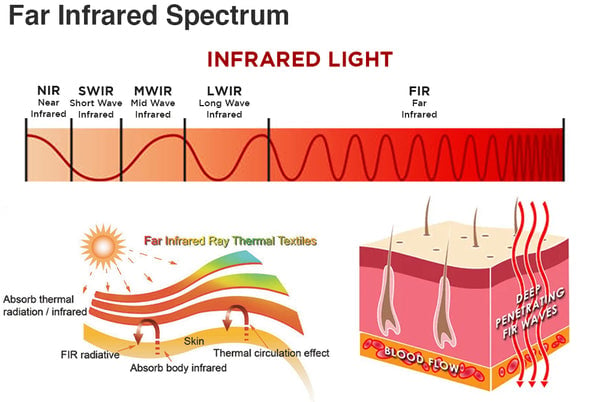

Είναι ρυθμιζόμενη η θερμότητα;

Όχι, η θερμότητα παράγεται φυσικά από τα σωματίδια του τουρμαλίνης σε επαφή με το δέρμα σας.